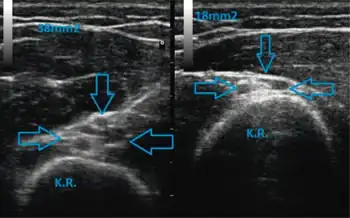

There are several mechanisms of nerve injury including mechanical lesions, ischemia, immunologic attack, metabolic disorder, toxic agents, and exposure to radiation.[6] The most common mechanism of injury is nerve compression in which external pressure causes decreased blood flow to the nerve and deformation of the nerve fibers.[6] Repeated or prolonged compression of the nerve results in ischemia and ultimately edema above and below the source of the pressure (I). The thinning of myelin sheaths or focal demyelination are the main consequences of the injury that lead to conduction blockage.[6]